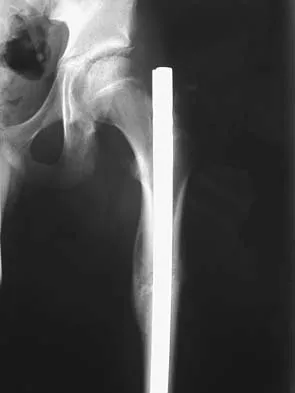

A 67-year-old patient seen in the emergency department reports the acute onset of pain and is unable to ambulate. History reveals that the patient underwent surgical treatment for a periprosthetic femoral fracture 6 months ago. A radiograph is shown in Figure 41. What is the best treatment option at this time?

The radiograph reveals a periprosthetic fracture at the tip of the stem with a stable cemented implant. This is classified as a Vancouver type B1 periprosthetic fracture. An attempt at internal fixation has already failed; therefore, the most predictable results would be achieved with distal fixation. After removal of the well-fixed cemented implant, the proximal bone may not be suitable for proximal fixation. Adequate bone stock is available such that an allograft prosthetic composite or a tumor prosthesis is not necessary. The best option is a long stem implant with distal fixation, which serves as an intramedullary device to restore alignment and increase the likelihood of union. Cortical onlay strut grafts are used as an adjunct to definitive fixation. Younger AS, Dunwoody I, Duncan CP: Periprosthetic hip and knee fractures: The scope of the problem. Inst Course Lect 1998;47:251-256.